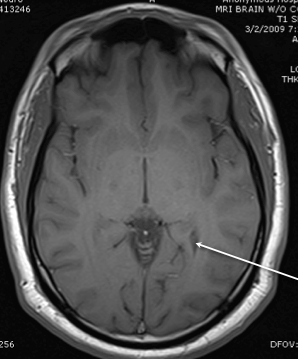

lateral ventricle

lateral horn

inferior ventircle

posterior horn of the internal capsule